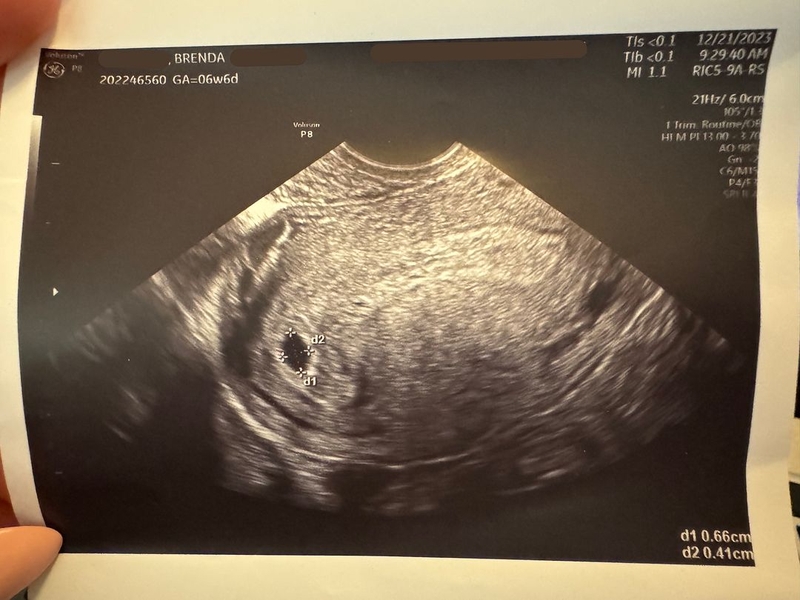

Thai 6 tuần túi ối méo chưa có phôi thai là một trong những tình trạng khiến nhiều mẹ bầu lo lắng không biết có ảnh hưởng, nguy hiểm đến thai nhi hay không. Để biết bác sĩ nói gì về vấn đề này, Nhà thuốc Long Châu mời bạn cùng theo dõi thông tin dưới đây.

Thai 6 tuần túi ối méo chưa có phôi thai chưa thể kết luận bất cứ điều gì về phôi thai nên mẹ bầu không nên quá lo lắng mà hãy tái khám định kì và nghỉ ngơi, ăn uống khoa học, lành mạnh. Trong bài viết hôm nay, Nhà thuốc Long Châu sẽ cùng bạn tìm hiểu thêm về hiện tượng này.

Đối với thai nhi ở tuần tuổi thứ 5 hoặc 6, việc túi thai bị méo hoặc túi thai chưa có phôi thai, chưa có tim thai,… thực ra chưa đủ dữ kiện để chắc rằng thai ngừng tiến triển. Vì vậy, nếu được chẩn đoán thai 6 tuần túi ối méo chưa có phôi thai, bạn cần giữ tinh thần bình tĩnh và lắng nghe thêm ý kiến từ bác sĩ.

Thông thường, với trường hợp mẹ bầu mang thai 6 tuần túi ối méo chưa có phôi thai, chuyên gia thường khuyến cáo nên thực hiện siêu âm lại trong 1 – 2 tuần sau đó hoặc tiến hành thêm xét nghiệm beta-hCG theo chỉ định để có đủ dữ liệu để chẩn đoán, xác định cụ thể trạng thái của thai nhi.

Túi ối sẽ phát triển và dần trở nên dày hơn từ tuần thứ 2 của thai kì và khi đến tuần thứ 10, chức năng của túi ối đã dần hoàn thiện. Thông thường túi ối có hình tròn và bao bọc thai nhi nhưng một số trường hợp mẹ bầu siêu âm lại thấy rằng túi ối bị méo, thậm chí túi ối méo từ tuần thai thứ 6.